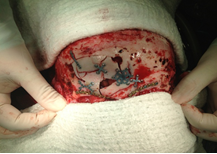

1) MARCO ESTEREOTAXIA: Marcación estereotáctica para lesiones profundas , craneotomias guiada por estereotaxia y/o asistidas por Neuronavegación. (Incluirá el equipo)

VI. CIRUGIA FUNCIONAL , ESTEREOTAXIA Y EPILEPSIA

Se prestará la asistencia para la alternativa terapéutica en casos de enfermedades refractarias a tto médico, cirugía en casos de movimientos